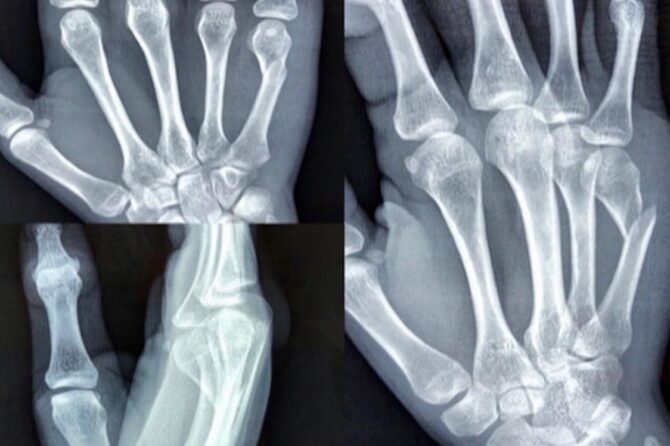

El Túnel Carpiano se manifiesta principalmente por hormigueos o adormecimiento en los dedos pulgar, índice, medio y mitad del dedo anular de la mano, y tiene mayor intensidad por las noches, obligando a veces al paciente a despertar y sacudir la mano.